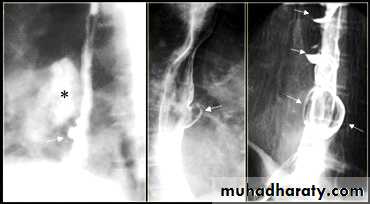

LEFT: Dilated esophagus (arrows) appears as long, well-defined structure paralleling heart RIGHT: Dilated esophagus usually deviates to right. Narrowing (arrow) at hiatus.

On the far left a traction diverticulum (arrow) due to hilar granulomatous disease. Calcified adenopathy (asterisk).

In the middle a pulsion diverticulum (arrow) due to high intra luminal pressure.

On the right multiple pulsion diverticula (arrows)